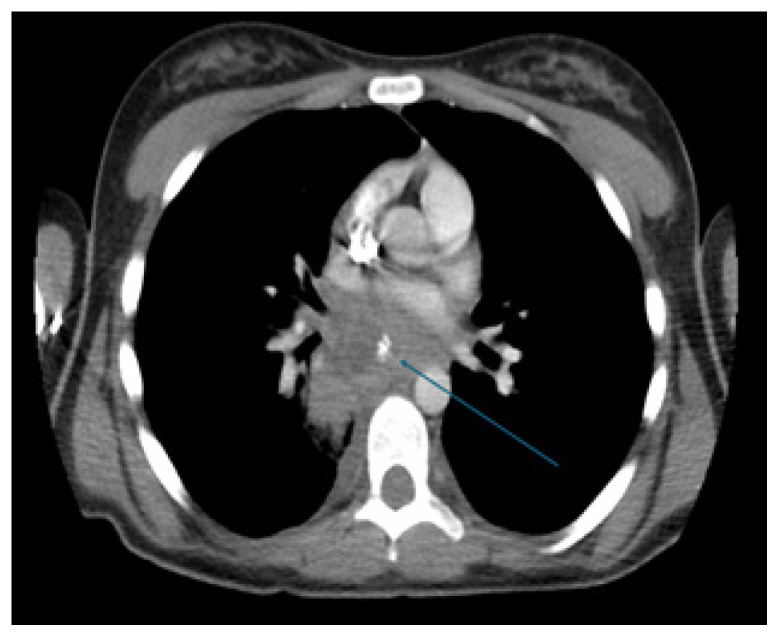

A Case Report of a Mediastinal Granuloma Related to Histoplasmosis with Streptococcus dysgalactiae Subspecies equisimilis Superinfection Resulting in Abscess and Subsequent Pericarditis in a Pediatric Patient.

Abstract Image